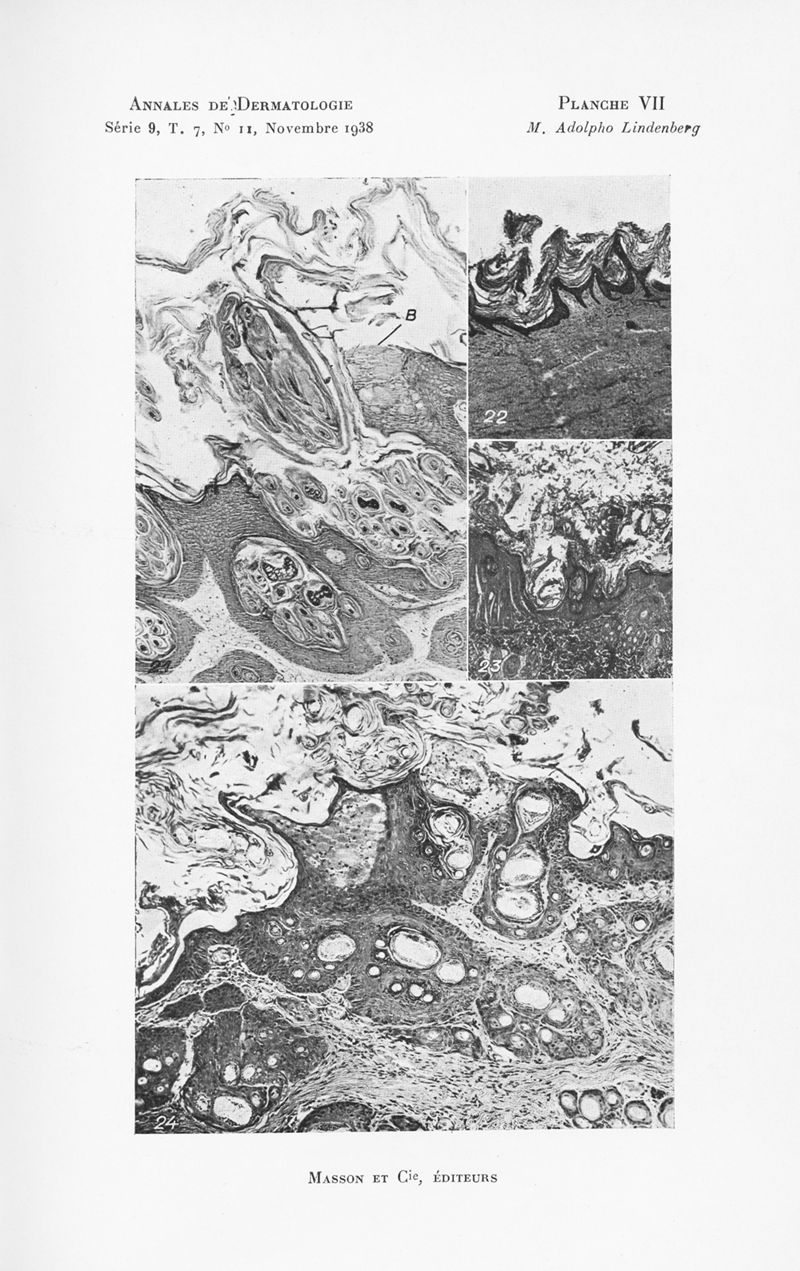

Annales de dermatologie et de syphiligraphie

7ème série, tome IX. - Paris : Masson, 1938.